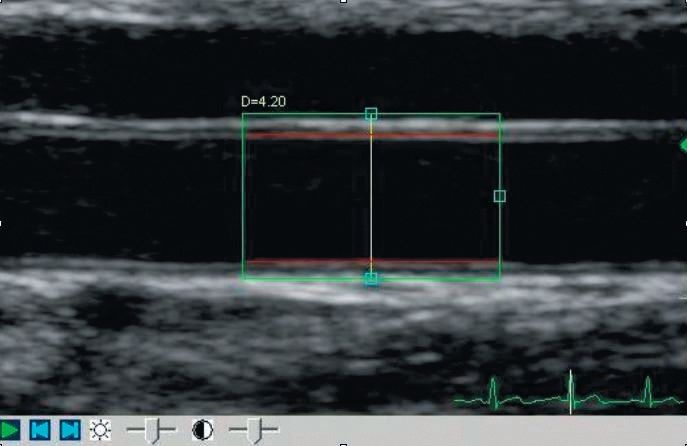

Die flussabhängige Dilatation (FAD) der A. brachialis ist eine der etabliertesten Methoden zur Messung der Endothelfunktion.

Diese wurde von Celermajer et al. 1992 erstmals beschrieben.

Nach einer 4,5 minütiger suprasystolischer Stauung des Unterarmes kommt es zu einer Scherkraft-vermittelten NO-Freisetzung aus den Endothelzellen, die eine reaktive Vasodilatation der A. brachialis zur Folge hat.

Das Ausmaß der Vasodilatation spiegelt das Ausmaß der NO-Produktion wider. Anhand hochauflösenden Ultraschalls wird der Gefäßdurchmesser der A. brachialis sowohl unter Ruhebedingungen, als auch 60–90 Sekunden nach dem Aufheben der Stauung bestimmt (Abb. 1).

Die prozentuelle Veränderung des Gefäßdurchmessers im Vergleich zum Ruhewert wird als FAD bezeichnet.